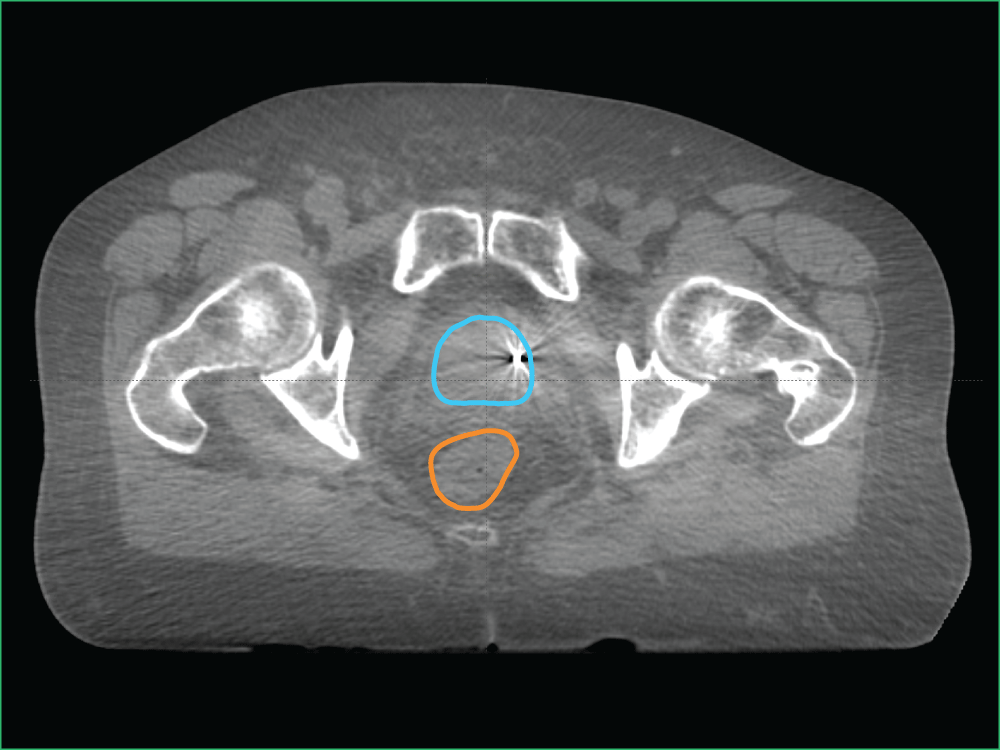

In images A, B and C, you can see the:

- Prostate in red

- Bladder in blue

- Bowel in orange

- Fiducial markers in white

- Planned target volume outlined in yellow (where the radiation will hit)

In image D, which is an example of a CBCT, you can see the:

- Planned target volume outlined in blue

- Bowel outlined in orange

This level of imaging is standard at GenesisCare and is used in our Linac machines for Image-Guided Radiation Therapy (IGRT) and Adaptive Radiation Therapy (ART).